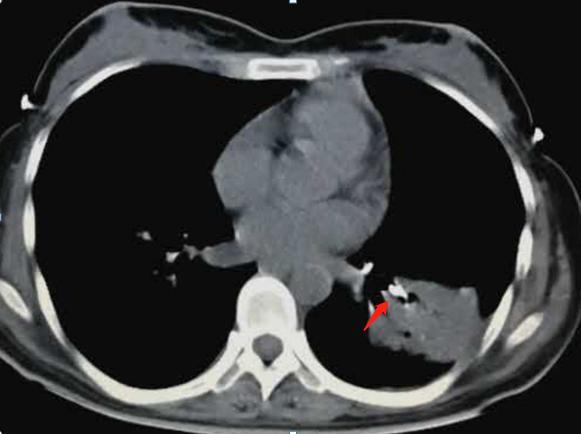

在左肺下叶的段支气管里果然发现灰白色异物,顺利钳取:

肺部炎症还需要进一步消炎治疗,不过已经无大碍。